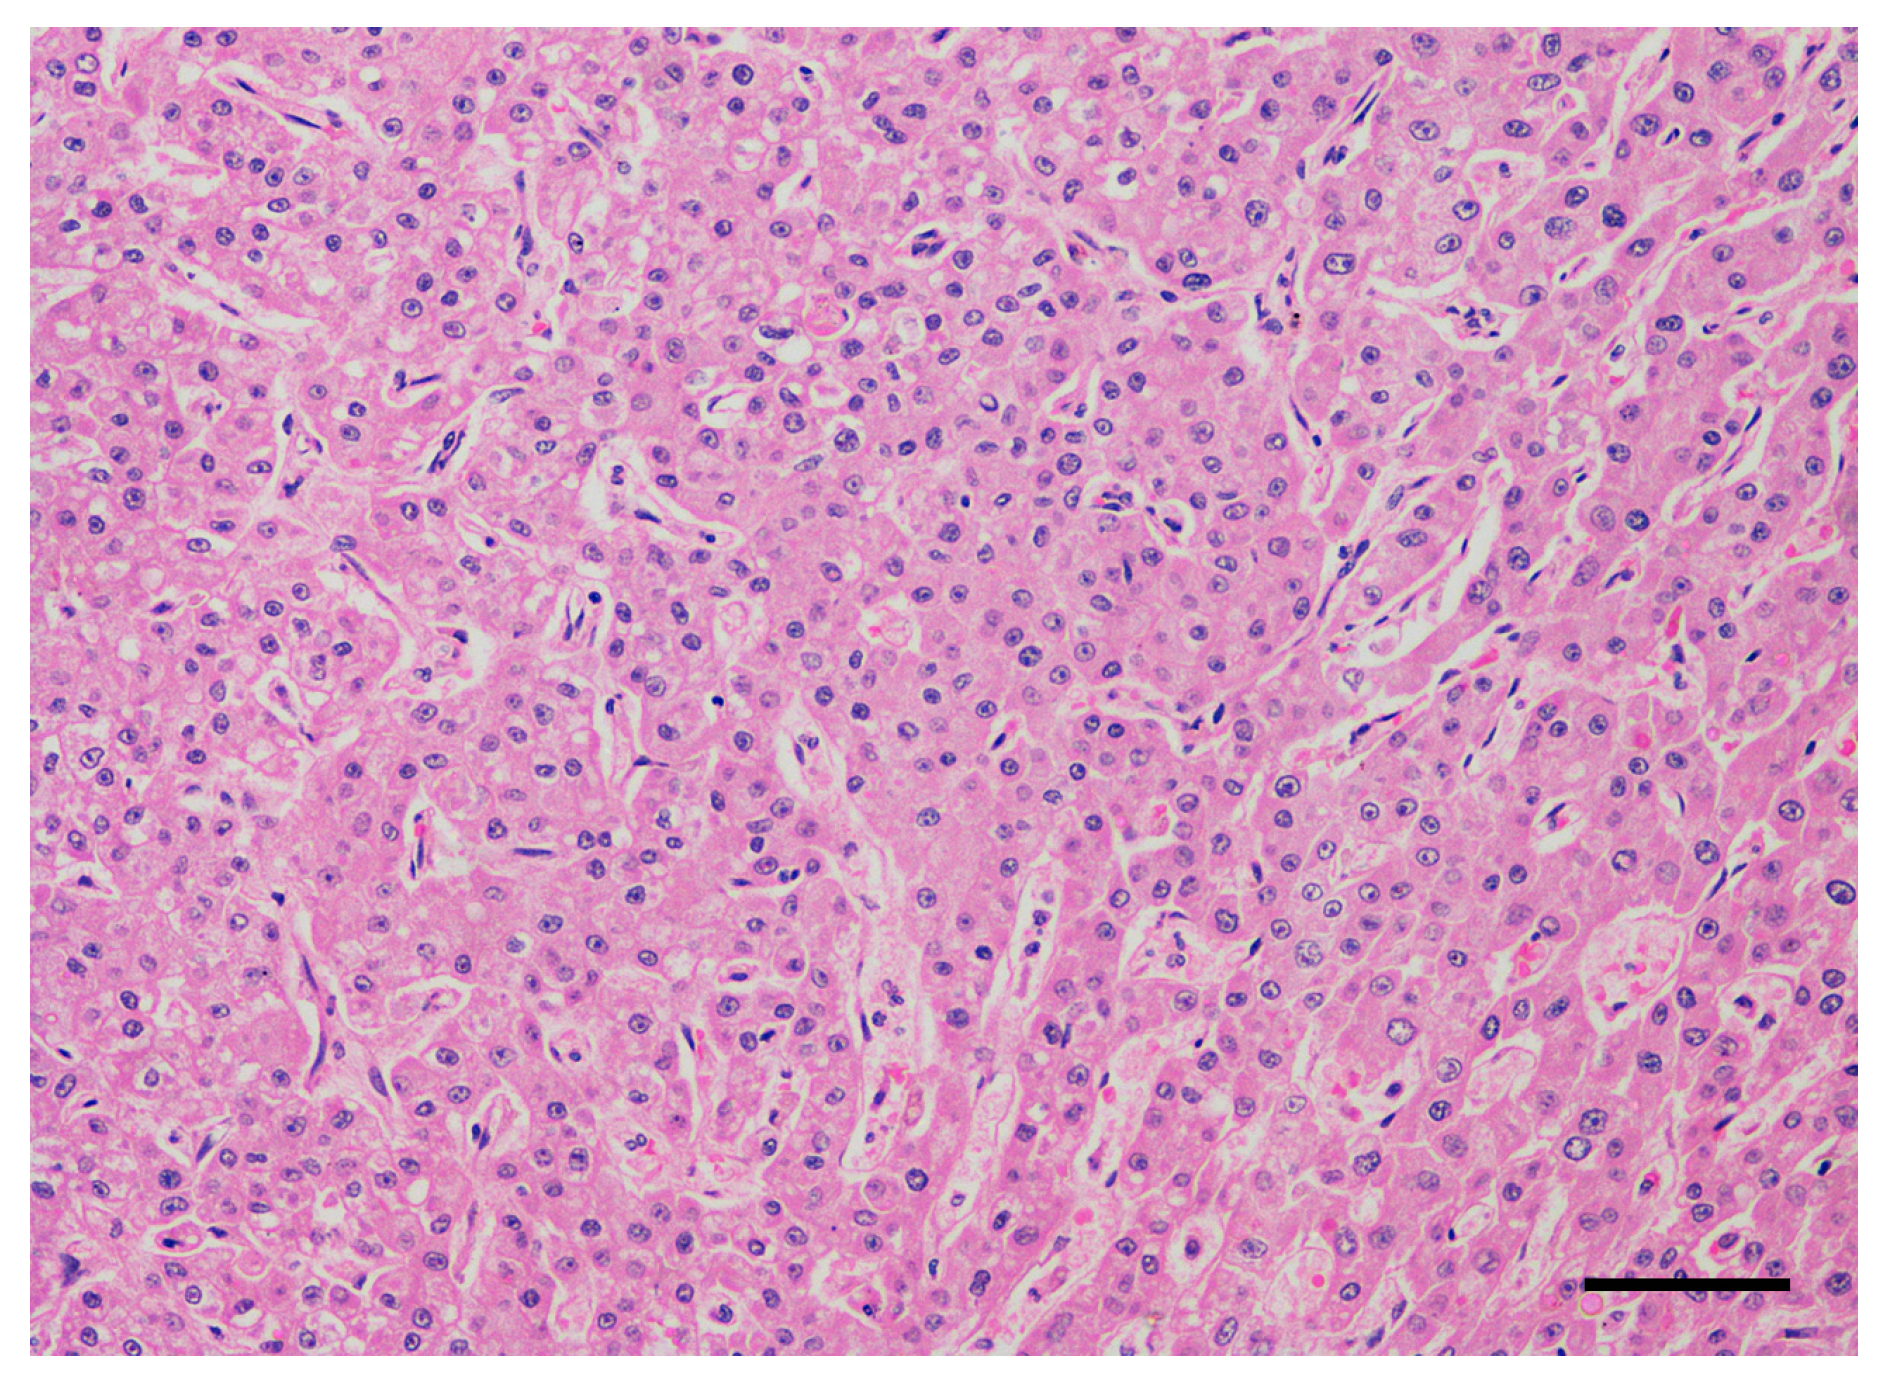

2.1. Dogs and Tumor Characteristics